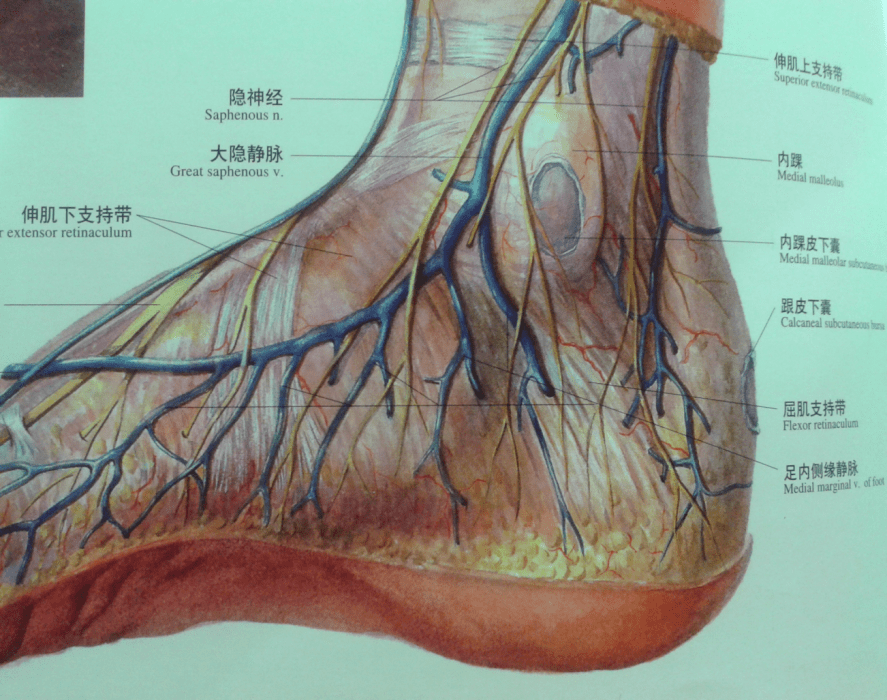

踝关节不稳定4踝伸肌下支持带解剖

图片尺寸826x1216

这里有最全的踝管综合征康复治疗方案!

图片尺寸960x440